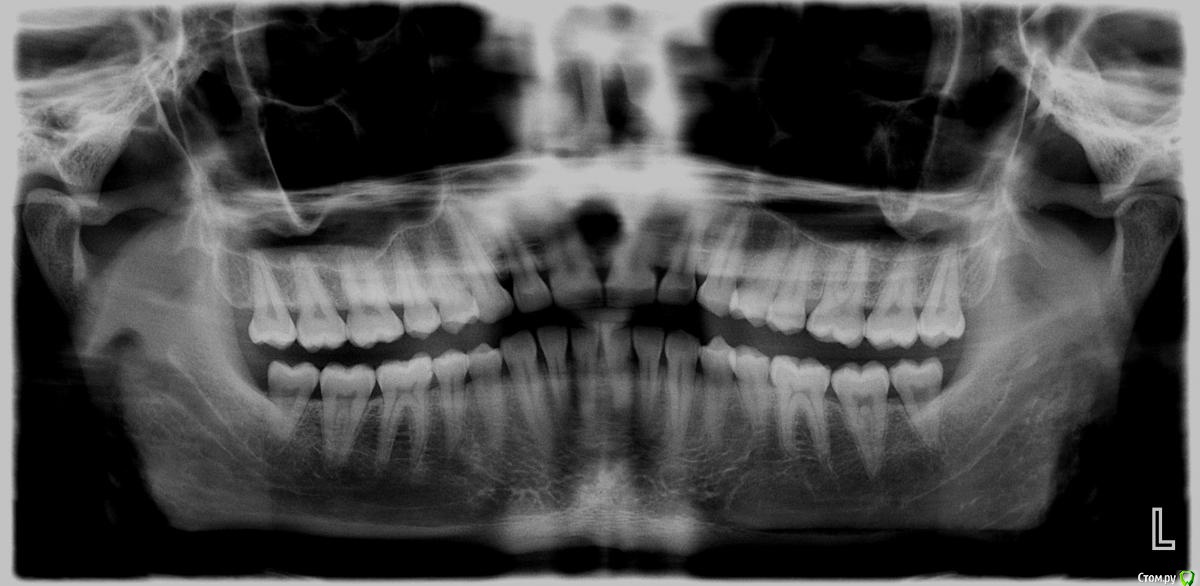

Манул Опубликовано 10 сентября, 2015 Поделиться Опубликовано 10 сентября, 2015 Здравствуйте. У меня боль в суставе челюстном слева, глаз отекает (мешок с утра). И при жевании боль в 6 зубе верхнем слева (если считать от центрального резца). Сделал панорамный, на нем всё нормально? Что делать, что может быть? Спасибо. Ссылка на комментарий

krokomot Опубликовано 10 сентября, 2015 Поделиться Опубликовано 10 сентября, 2015 По вашему снимку видимой патологии не наблюдается, нужно обратиться непосредственно на прием, если беспокоят зубы проверить их на витальность. Это все можно сделать только в клинике форум вам тут не поможет все будет только пальцем в небо. Ссылка на комментарий

Манул Опубликовано 11 сентября, 2015 Автор Поделиться Опубликовано 11 сентября, 2015 По вашему снимку видимой патологии не наблюдается, нужно обратиться непосредственно на прием, если беспокоят зубы проверить их на витальность. Это все можно сделать только в клинике форум вам тут не поможет все будет только пальцем в небо.Проблема в том, что зубы все интактны (стучали и воздушной струей проверяли), я у многих врачей был у 3 хирургов, 5 парадонтологов, 2 терапевтов..."У вас всё в норме!"А боль не проходит, есть не могу и глаз отекает (как фингал под глазом небольшой).Окулист сказа его патологии нет, у ЛОРа пока не был, но заложенности носа нет...Я не знаю что делать, всё в норме, а всё болит. Я не могу сказать, что идет усиление боли со временем, но и не проходит ничего. Ссылка на комментарий

krokomot Опубликовано 11 сентября, 2015 Поделиться Опубликовано 11 сентября, 2015 На проверить зубы методом электроодонтодиагностики, если и по этому методу они все здоровы, то тогда смотреть пазуху и нос. Отек может вызывать тромбоз вен. В любом случае ответит вам не видя вас очень сложно. Ссылка на комментарий

shishok Опубликовано 11 сентября, 2015 Поделиться Опубликовано 11 сентября, 2015 Учитывая горький опыт моей знакомой,я бы ещё и КТ головы сделала. Ссылка на комментарий